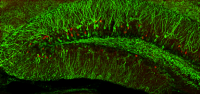

developed that enables her to detect recorded and recalled memories in the brain. In these mice, a yellow fluorescent dye permanently marks the neurons when they record a new memory. When the mice recall that memory, a red fluorescent dye permanently marks the active cells. Cells with overlapping yellow and red labels represent what is called a memory trace.

In the study, lead author Jennifer Perusini, PhD, used a line of mice that Dr. Denny previouslyDr. Denny and her team then examined memory formation and retrieval in healthy and Alzheimer’s mice. Both sets of mice learned to associate a lemon scent with a mild electric shock. That memory was tested a week later when the mice were re-exposed to the scent. The healthy mice remembered the lemon scent and its consequences: They froze with fear. In contrast, the Alzheimer’s mice had trouble remembering and froze about half as often as their healthy counterparts.

When the researchers looked at the neurons of the Alzheimer’s disease mice to identify the problem, they saw the yellow marker that indicated the memory had been recorded. But different neurons were marked red, suggesting that the mice recalled a different memory.

The Alzheimer’s mice were able to recall the correct memory with a little help from the researchers. Using laser light to stimulate the memory-storing neurons, the “lost” memory was accessed.